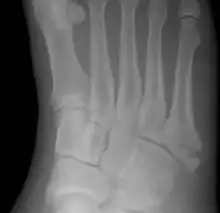

| Jones fracture as seen on Xray | |

The fracture typically occurs when the toes are pointed and the foot bends inwards.[6][2] This movement may occur when changing direction while the heel is off the ground such in dancing, tennis, or basketball.[9][10] Diagnosis is generally suspected based on symptoms and confirmed with X-rays.[3]

Diagnostic x-rays include anteroposterior, oblique, and lateral views and should be made with the foot in full flexion.